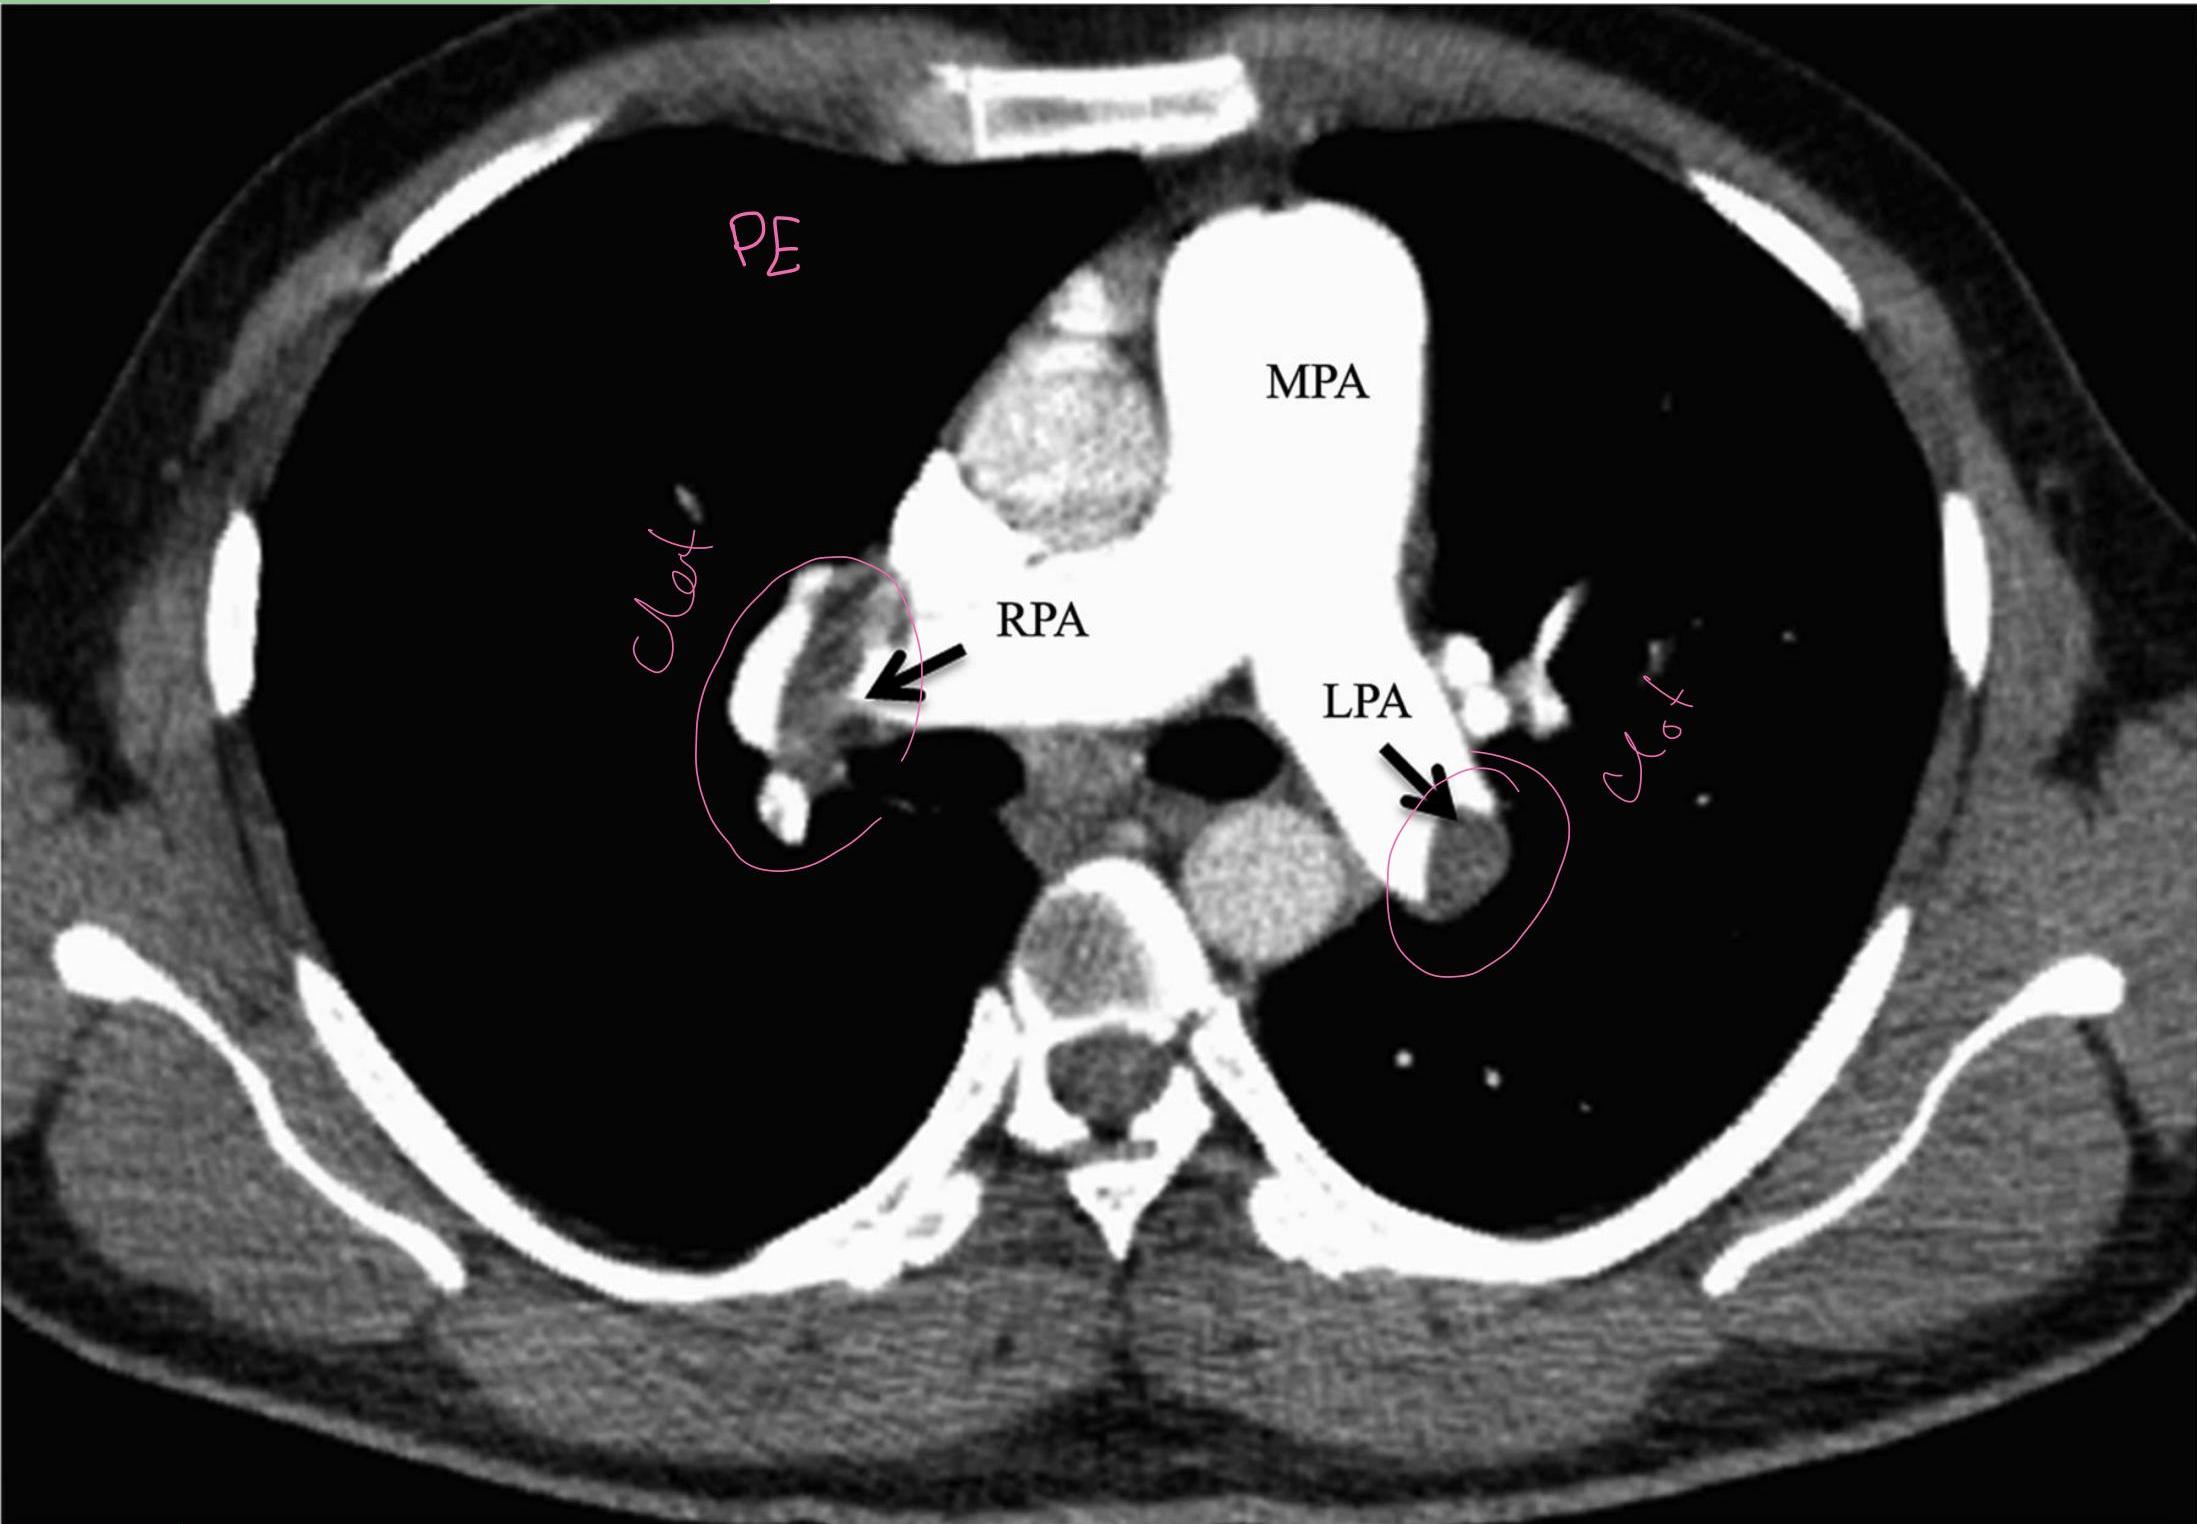

Pulmonary Embolism (CT Angio):